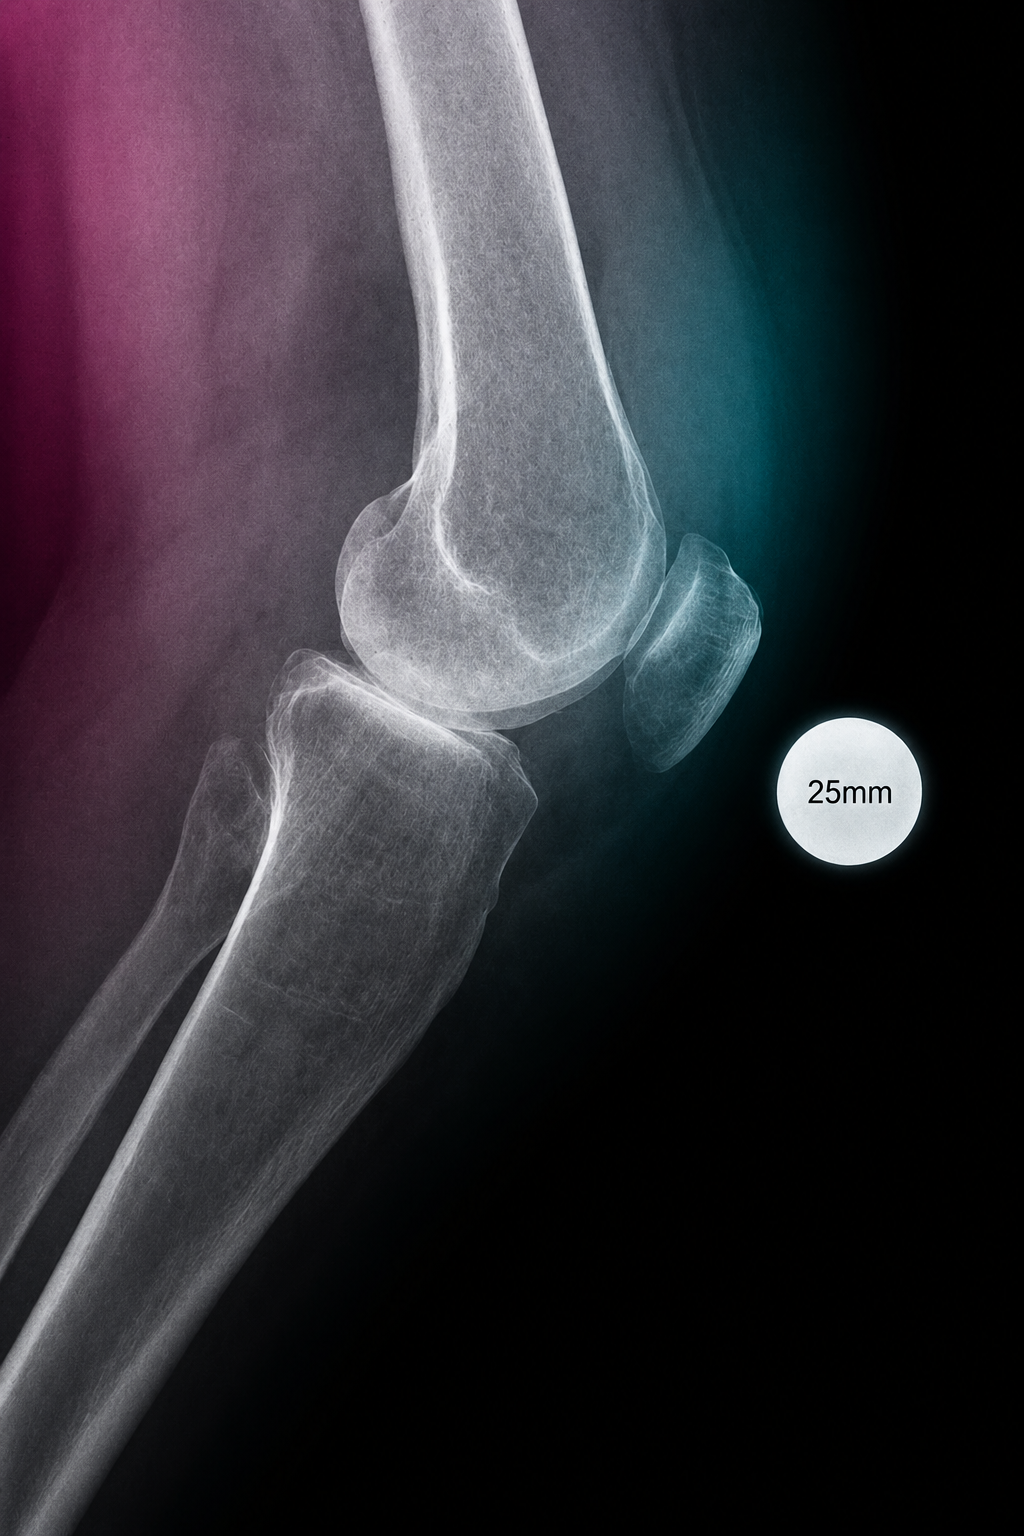

A compact guide for radiology teams on correct calibration sphere placement in orthopedic X-ray imaging. The marker must be positioned in the anatomical plane of the target joint so that digital scaling, measurements and preoperative templating remain clinically reliable.